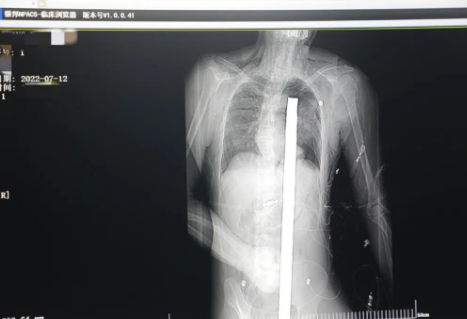

突發(fā)!太疼了,1.2米長(zhǎng)的螺紋鋼從男子會(huì)陰部垂直穿入胸腔......7月12日下午16時(shí)10分,西安一處工地的一名26歲工友,不慎從10多米的高空墜落,不幸的是工地上一根直徑3厘米的螺紋鋼從男子會(huì)陰部垂直穿入體內(nèi),工地上的工友們小心翼翼地將連著的鋼筋截?cái)唷G闆r危急,立即送往西安國(guó)際醫(yī)學(xué)中心醫(yī)院急救中心,此時(shí)正是下午17時(shí)00分。

時(shí)間就是生命!此時(shí),西安國(guó)際醫(yī)學(xué)中心醫(yī)院展開了一場(chǎng)與生命賽跑的搶救,第一時(shí)間開辟綠色通道,急診X光片及CT顯示:異物經(jīng)會(huì)陰部貫穿盆腔、腹腔到達(dá)左側(cè)胸腔主動(dòng)脈弓水平。醫(yī)院創(chuàng)傷中心立即啟動(dòng)應(yīng)急預(yù)案,劉延彤副院長(zhǎng)親臨指揮,下午17點(diǎn)48分,當(dāng)患者被送達(dá)手術(shù)室,胸外、心外、肝膽外科、胃腸外科,泌尿外科及麻醉科等多學(xué)科專家聯(lián)手對(duì)這名工友進(jìn)行“縱劈胸骨 前外側(cè)開胸探查 氣管及主支氣管修補(bǔ) 肺修補(bǔ) 血胸清除 開腹探查止血 腹膜后及盆腔探查......”手術(shù)。

情況緊急!術(shù)中探查后發(fā)現(xiàn),長(zhǎng)120cm直徑3cm的螺紋鋼經(jīng)患者右側(cè)會(huì)陰部穿入,傷及直腸,途徑膀胱后方,左側(cè)髂總動(dòng)靜脈之間傷及左腎后,經(jīng)胰腺后方在肝脾之間穿破膈肌,在下肺靜脈前方穿入左肺穿破氣管及左右主支氣管膜部,止于主動(dòng)脈弓下水平,穿入體內(nèi)的部分達(dá)到75cm。